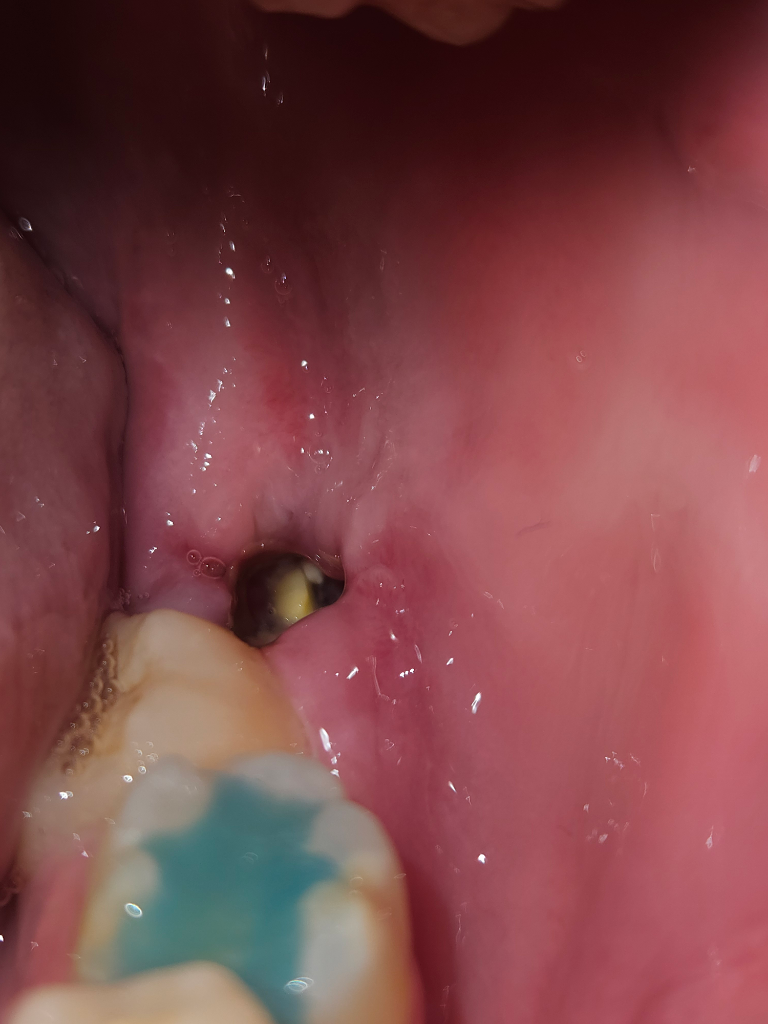

사랑니 발치 5일차인데, 이거 드라이 소켓인가요?

통증도 아직 남아있고, 이물감이 있어서 거울을 봤는데 저렇게 되어 있네요.. 저거 드라이 소켓으로 나타난 뼈인가요 아니면 이물질인가요?

정상적인 치유 과정으로 보여지며 현재 상태에서 정확한 판단이 어렵지만 일부 음식물도 끼어 있는 것으로 보여집니다. 드라이소켓이라면 2~3일 지난 시점에서 극심한 통증이 나타나고 약간의 통증이 있는 것이 아닙니다. 현재 잇몸 반응으로 보아서는 정상적인 회복 과정으로 보여집니다.

해당부위에 혈병이 형성된 것으로 보이며, 상처가 나아가는 과정으로 걱정하지 않으셔도 되며, 시간이 지나면 저절로 없어지게 됩니다.

드라이소켓의 양상은 아닌 것으로 보입니다. 발치 후 일주일까지도 약간은 통증이 남아있을 수 있습니다. 통증이 점차 사라지는지 아니면 심해지는지를 지켜보시기 바랍니다

이물질 같습니다. 드라이소켓은 통증이 남아있다 정도가 아닌 극심한 통증이 나타나야 합니다.

드라이 소켓은 아닌거 같습니다. 드라이 소켓은 감염의 일종으로 냄새도 많이 나고 통증이 극심합니다. 너무 걱정하지 않으셔도 될것같습니다.